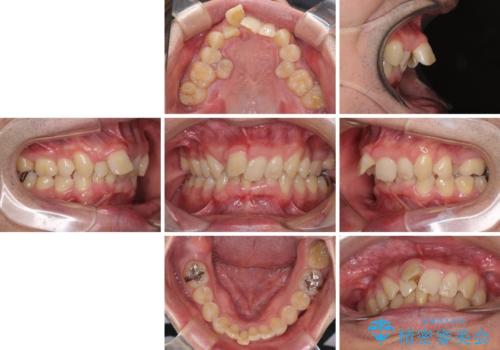

- ぶつけて前歯が折れてしまったとのことで来院された患者様です。

折れてしまった前歯は軽傷であり、歯内の歯髄に影響は及んでいませんでした。

通常では速やかにオールセラミッククラウンにて補綴治療を行うのですが、デコボコしている歯列も気になっていたため、事前に矯正治療を行うこととしました。

上顎歯列の叢生が著しかったため、上顎左右第一小臼歯2本を抜歯し、目立たないワイヤー装置にて治療を進めることとしました。